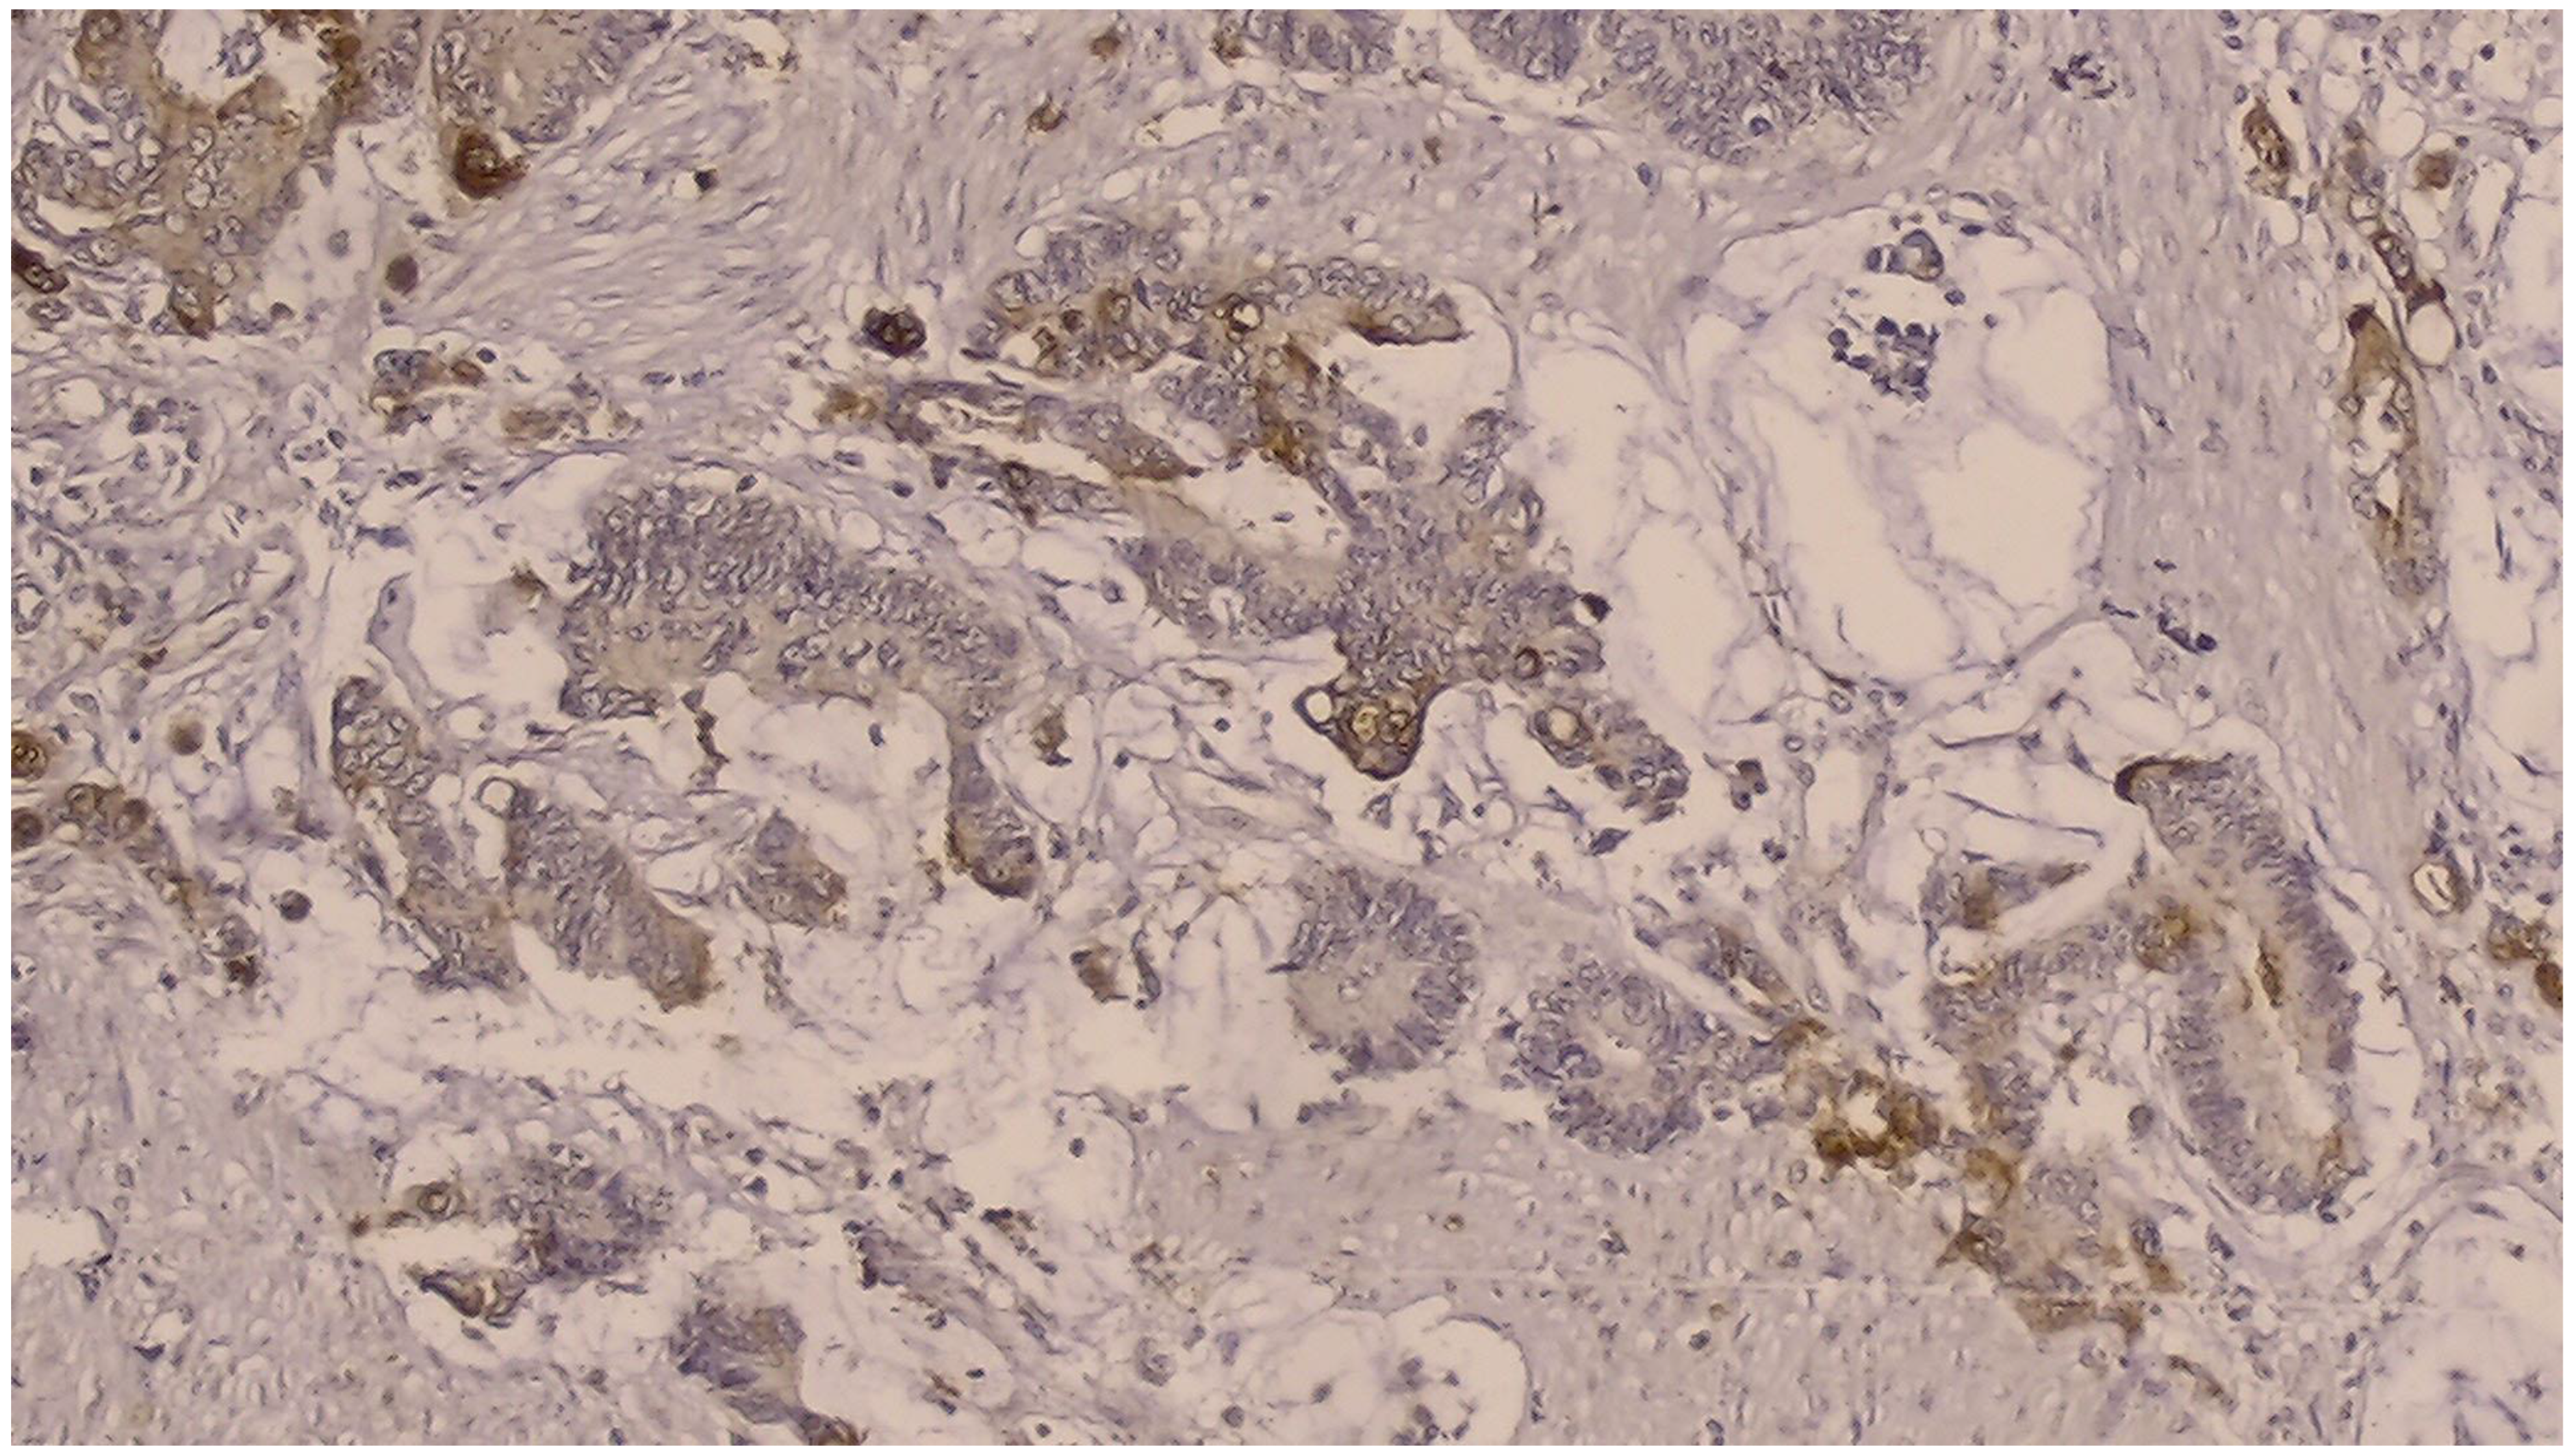

NGAL positivity was defined as diffuse or patchy areas of strong cytoplasmic and/or nuclear staining [Figure 1]. In addition, we counted the number of NGAL positive inflammatory cells that infiltrated the tumors per HPF, which was defined as NGAL positivity in the tumor microenvironment [Figure 2]. KIM-1 positivity was described as diffuse or patchy areas of strong cytoplasmic staining [Figure 3]. Since no tumors with nuclear NGAL expression alone were found, the tumors could not be grouped as nuclear and cytoplasmic expression. For both antibodies, strong focal staining or diffuse but very weak staining visible under a microscope was regarded as KIM-1 or NGAL negativity. Both antibodies were not scored because very weak staining was considered as negative.

Figure 1.

Immunohistochemically, cytoplasmic and a few intensely nuclear stained NGAL-positive tumor cells (DAB × 200).